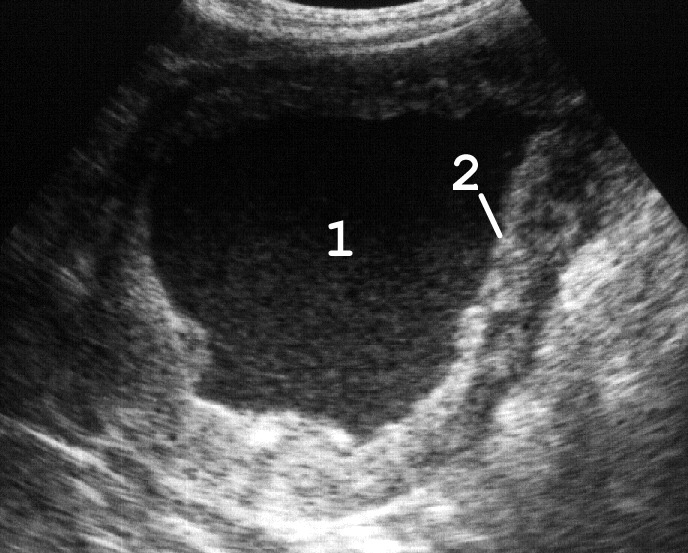

Уретероцеле может быть простым (при нормальном расположении устья) и эктопическим (при его эктопии), одно- и двухсторонним. Часто встречается уретероцеле одного из удвоенных мочеточников. При ультразвуковой цистоскопии уретероцеле обнаруживается как кистовидное расширение терминального отдела мочеточника, размеры которого изменяются при систоле и диастоле нижнего цистоида мочеточника (рис. 14).

Рис. 14. Сонограммы мочевого пузыря с уретероцеле: 1 − мочевой пузырь; 2 − уретероцеле; 3 − горизонтальный уровень эхогенного осадка при пиурии. (Поперечное сканирование, секторный датчик 5 МГц, “Siemens SL-1”).